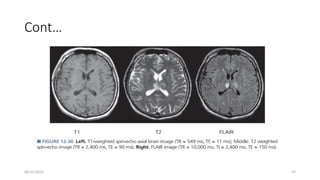

T1 Weighting

• A “T1W” SE sequence is designed to produce contrast chiefly based on the T1

characteristics of tissues,

• with de-emphasis of T2 and proton density contributions to the signal.

• Achieved by using a relatively short TR to maximize the d/c in longitudinal

magnetization recovery during the return to equilibrium,&

• a short TE to minimize T2 decay during signal acquisition

• T1W SE contrast requires a short TR and a short TE (spin-lattice relaxation time)

• Fat is the most intense signal, followed by white matter, gray matter, and CSF.

T2 Weighting(T2W)

• T2 contrast weighting follows directly from the PD-weighting sequence

• reduce T1 differences in tissues with a long TR, and emphasize T2 differences

with a long TE.

• The T2-weighted signal is generated from the second echo produced by a second

180-degree pulse of a long TR spin echo pulse sequence,

• where the first echo is proton density weighted, with short TE.

cont…

• T2 contrast differences are manifested by allowing M xy signal decay .

• Compared with a T1-weighted image, CSF is bright, and gray and white matter

are reversed in intensity.

• As TE is increased, more T2-weighted contrast is achieved.

• but at the expense of less M xy signal and greater image noise.

Fluid Attenuated Inversion Recovery

• used exclusively in brain and spine imaging, to null CSF signals in a T2w image.

• Helpful to distinguish periventricular lesions from the high signals in ventricles.

• Since CSF has a very long T1, a long TI is needed (1700–2500 ms).

• There is a wide range of TIs because the signal is changing only slowly;

• a few tens of ms difference can still give adequate CSF suppression.

• At such long TIs, all other tissues already have positive Mz & in fact may be close

to |M0|.

• A long TE is used to create T2w contrast.